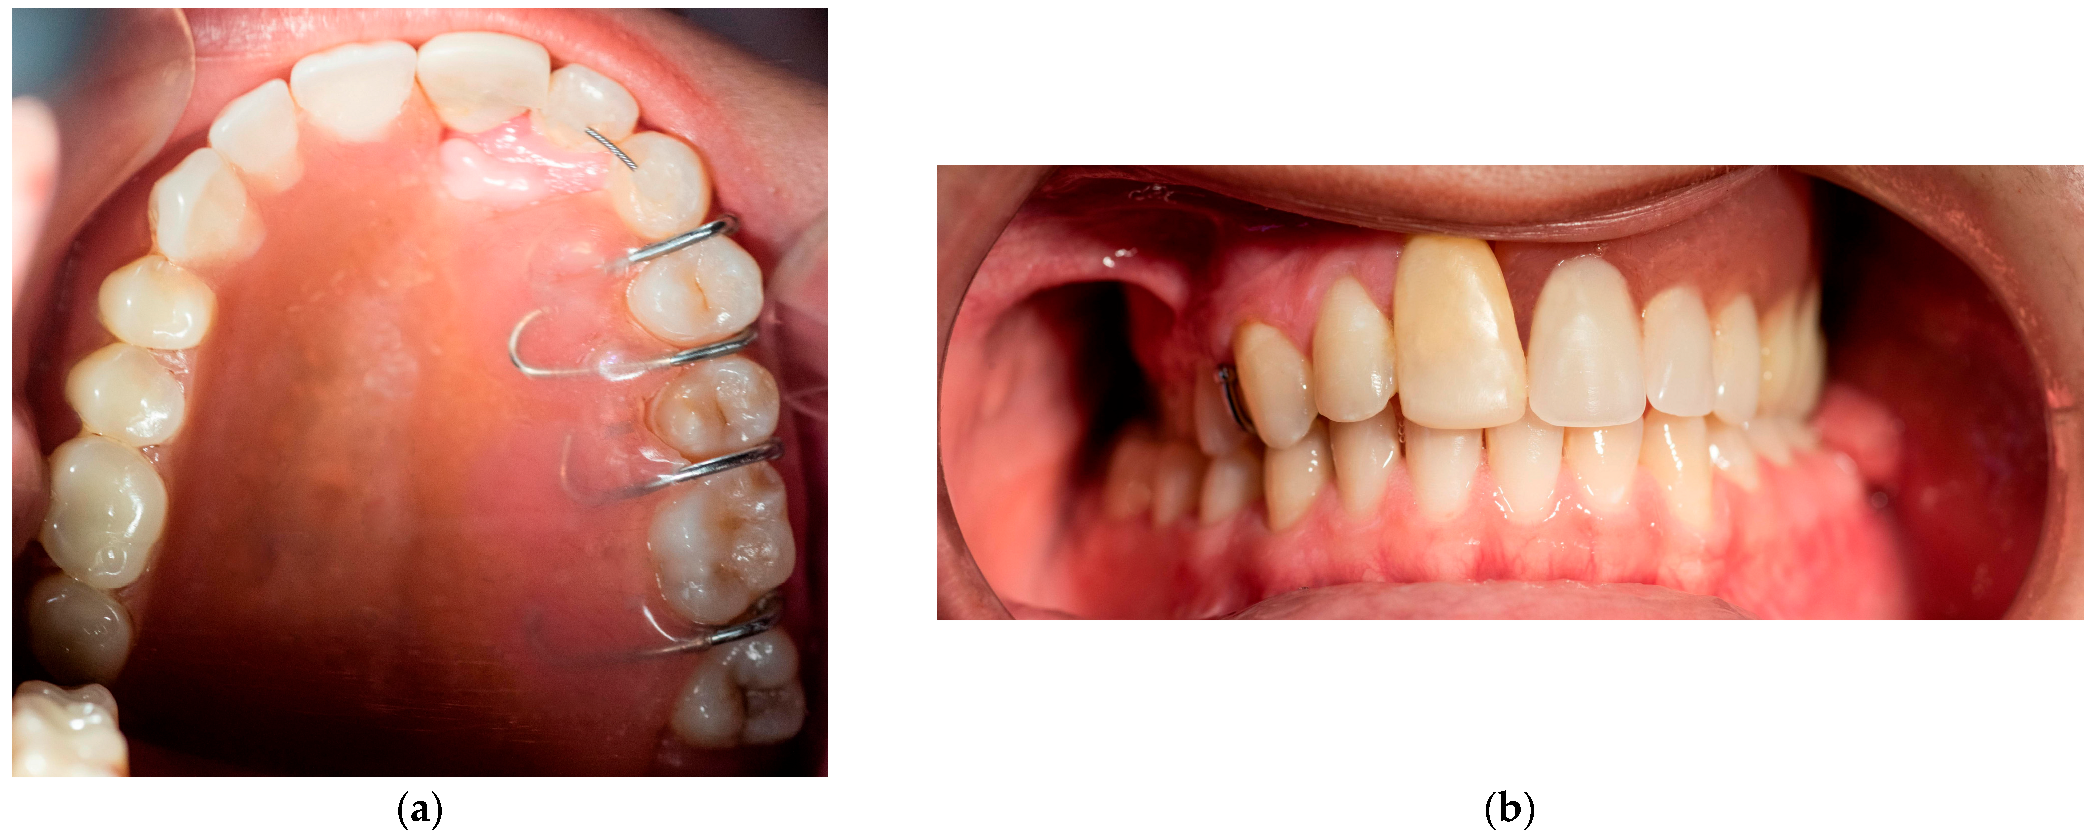

The fibroma was surgically excised. A bone graft harvested from the right scapula was placed in the defective area; however, due to the lack of vascularization, the graft was rejected. A second graft, taken from the left scapula, was also unsuccessful. Later on, a custom removable appliance was manufactured to restore function, esthetics, and facial contour of the stomatognathic system. The prosthesis on the dental cast is shown in Figure 1a, while Figure 1b shows the frontal view of the same cast. The occlusal anatomy of the edentulous defect is visualized in Figure 2a. The upper right central incisor was intruded, and a tooth extension of the removable appliance in #11 space was added. The appliance extended into the defective area, and an important feature was the hollow design of the segment extending into the sinus cavity, which contributed to increased retention while minimizing weight (Figure 2b). Over the course of time, the appliance had been periodically modified as needed to accommodate craniofacial growth and the development of neighboring structures. By October 2023, the patient had undergone orthodontic tooth movement with fixed appliances for space closure of the upper right quadrant. A panoramic radiograph was obtained, demonstrating the left-sided maxillary resection and completed orthodontic space closure, with preserved dental alignment on the contralateral side (Figure 3).

The removable appliance was designed to restore the left side of the maxillary space defect. It replaced the base of the maxilla and extended into an oval projection that partially occupied the maxillary sinus space. This projection was bordered by a shallow peripheral groove, which played a critical role in the retention of the appliance (Figure 5a). The prosthesis was further stabilized by four 0.7 mm metal ball clasps, positioned in the interproximal spaces between the canine, premolars, and molars on the contralateral side of the defect (Figure 5b). Intraoral examination confirmed proper adaptation of the appliance, as demonstrated in the occlusal (Figure 6a) and frontal intraoral views (Figure 6b).

Figure 1. (a) Occlusal photograph of the previous prosthesis in dental cast. (b) Frontal photograph of the previous prosthesis in dental cast.